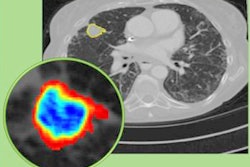

Radiomic feature maps of pretreatment CT show differences between lesions in responders and lesions in nonresponders. There appears to be overexpression of radiomic features (A, peritumoral Gabor, and B, intratumoral Laws features) in the nonresponder lesion compared with the responder lesion. The distribution of the features shows significant differences between the two lesion categories; these differences are captured by the skewness and kurtosis statistics of the feature distribution. Images courtesy of Radiology: Artificial Intelligence.The combination of radiomics features with a quadratic discriminant analysis classifier produced a mean area under the receiver operating characteristic curve (AUC) of 0.82 in the training set and 0.77 in the independent testing set for predicting response to chemotherapy. Furthermore, the radiomics risk-score signature -- calculated via regression analysis -- was significantly associated with time to progression (hazard ratio, 2.8; p < 0.0001) and overall survival (hazard ratio, 2.35; p < 0.0011).